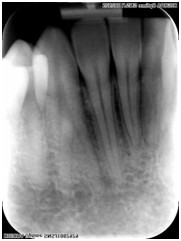

Zdjęcie rentgenowskie przedstawia dwukorzeniowy kieł żuchwy. Częstość występowania w tym zębie dwóch kanałów i dwóch korzeni wynosi odpowiednio:

Pytanie 103